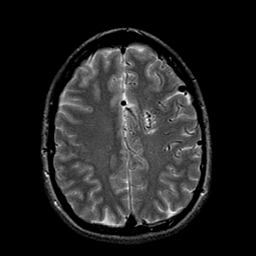

Vascular Malformation:T2-weighted MR #1 -- Slice #17

[Home][Help][Clinical] Slice 17